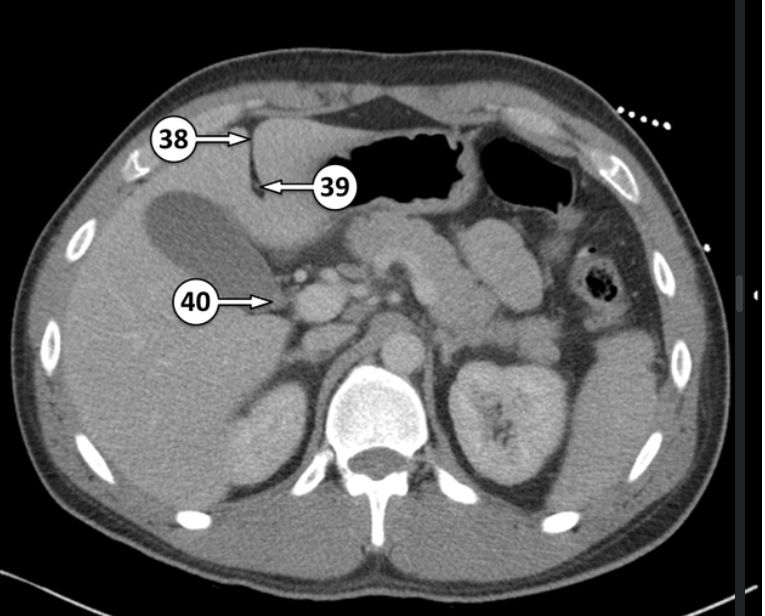

What is 38 and 40?

Falciform ligament

neck of the gallbladder